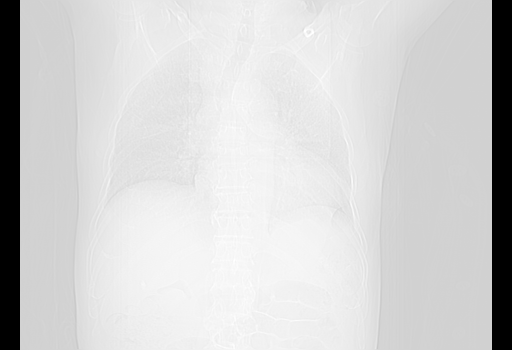

经过24天治疗,岳父的病情基本稳定。生活基本可以自理,可以下床活动。呼吸困难早已消失。体温基本正常。

主要治疗甲强龙80mg×14天,60mg×10天;同时抗结核(异烟肼+利福平+乙胺丁醇)。环磷酰胺0.1 tid 10天。

特别感谢胡教授、高管、桃子版主给出关键的治疗建议。桃版把所有肺部影像和全部临床资料请所在医院呼吸科、感染病科、结核科、临床免疫科专家会诊。临床免疫科专家制定了完整的治疗方案。